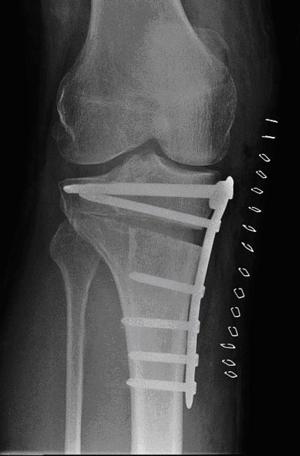

Bij de ingreep maakt de operateur een snede in het onderbeen. Hierna wordt het bot van het onderbeen bereikt. Bij de open-wig osteotomie wordt het bot van het scheenbeen ingezaagd en open gespreid. Op de plaats waar de wig uit het scheenbeen verwijderd is, plaatst de arts een plaat met schroeven. Hierdoor wordt de gecorrigeerde beenstand gefixeerd. Het plaatje en de schroeven liggen onder de huid. Het kuitbeen blijft intact. Vervolgens wordt de huid gesloten en wordt een drukverband aangelegd.